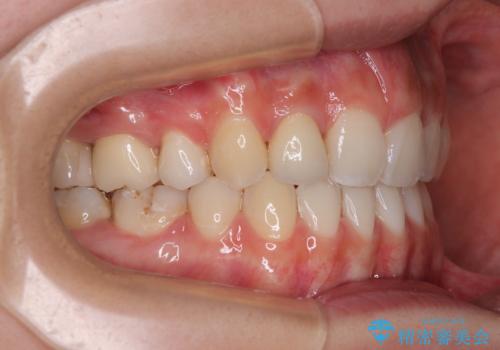

下顎の抜歯位置を左右で変えることで、最終的に上下正中をほぼ一致させることができました。

また上顎前歯は大臼歯に補綴治療が必要であったため、矯正治療後にオールセラミッククラウンによる補綴治療を行うこととしました。